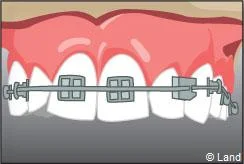

La technique linguale offre la possibilité d’un appareil orthodontique efficace et totalement invisible.

Elle permet la pose de bagues sur la face interne des dents. Elle est souvent utilisée pour les traitements de l’adulte rebutés par le port d’un appareil visible. Cette technique difficile à mettre en ?uvre et peu confortable pour le patient, a fortement évolué ces dernières années, notamment grâce à la conception et à la réalisation assistées par ordinateur. On peut donc aujourd’hui traiter tous les patients qui le souhaitent en lingual.